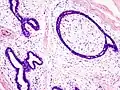

| Histopathologic image of breast fibroadenoma. Core needle biopsy. H&E stain. | |

Histopathologic image of breast fibroadenoma. Core needle biopsy. Hematoxylin & eosin stain. -